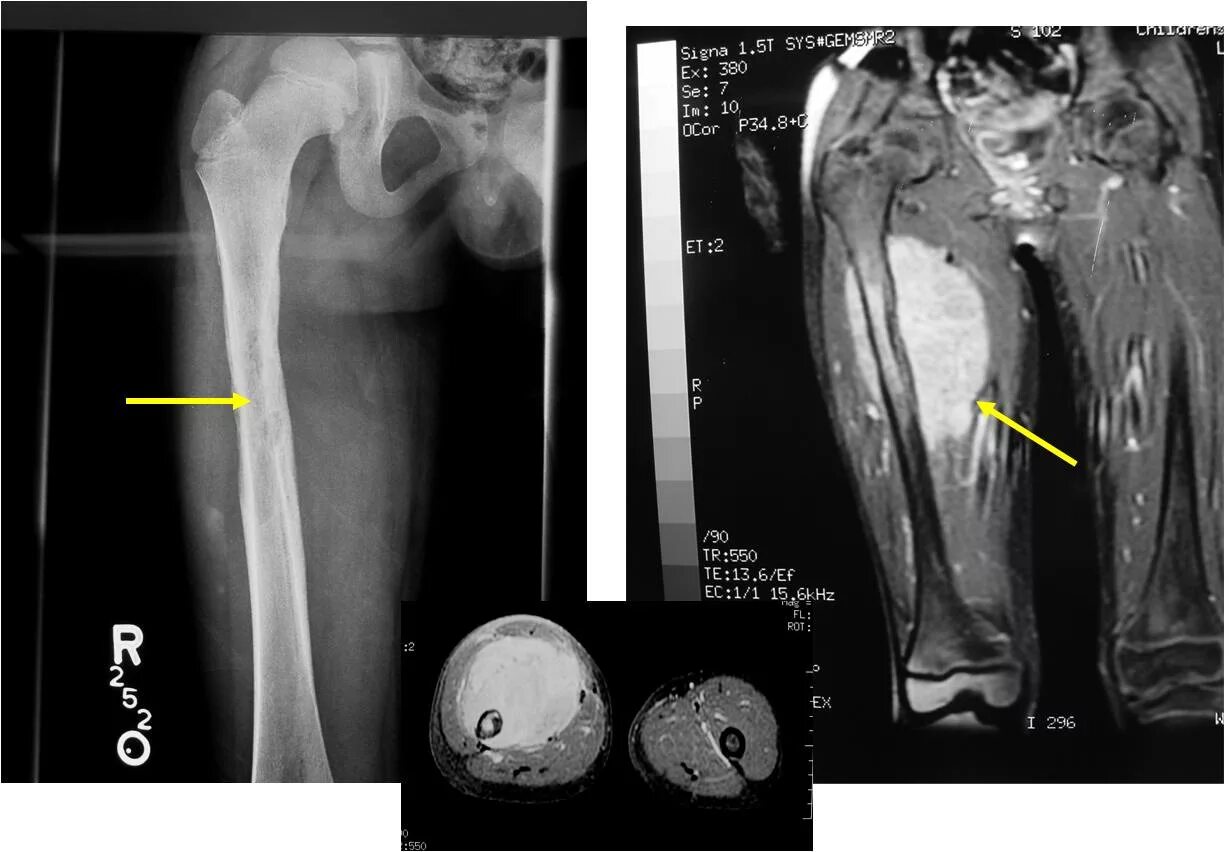

Саркома мрт